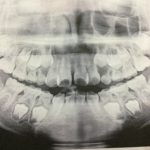

Juri*歯列矯正(2回目)

2018/12/18

さて! 今日は歯列矯正2回目でございます♫ 装置を装着していくのは 年明けからになるんだけど、着々と計画が進んでるから楽しみだね! 今日は 前回、撮影したレントゲンや姿勢・歯の状態や 今後、どうやって ...